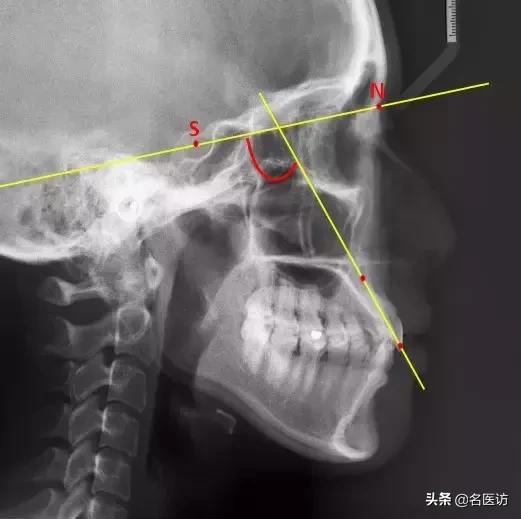

4、评估上下唇凸度:E线

Prn:鼻部最凸点

Pog’:颏部最前点

E线也叫审美平面,是鼻子凸点和颏前点的切线,用来评估上下唇的凸度。据统计,中国成年人上下唇超出E线的占76%,而美丽的成年女性,双唇应该都在E线内。(手动微笑再见!)